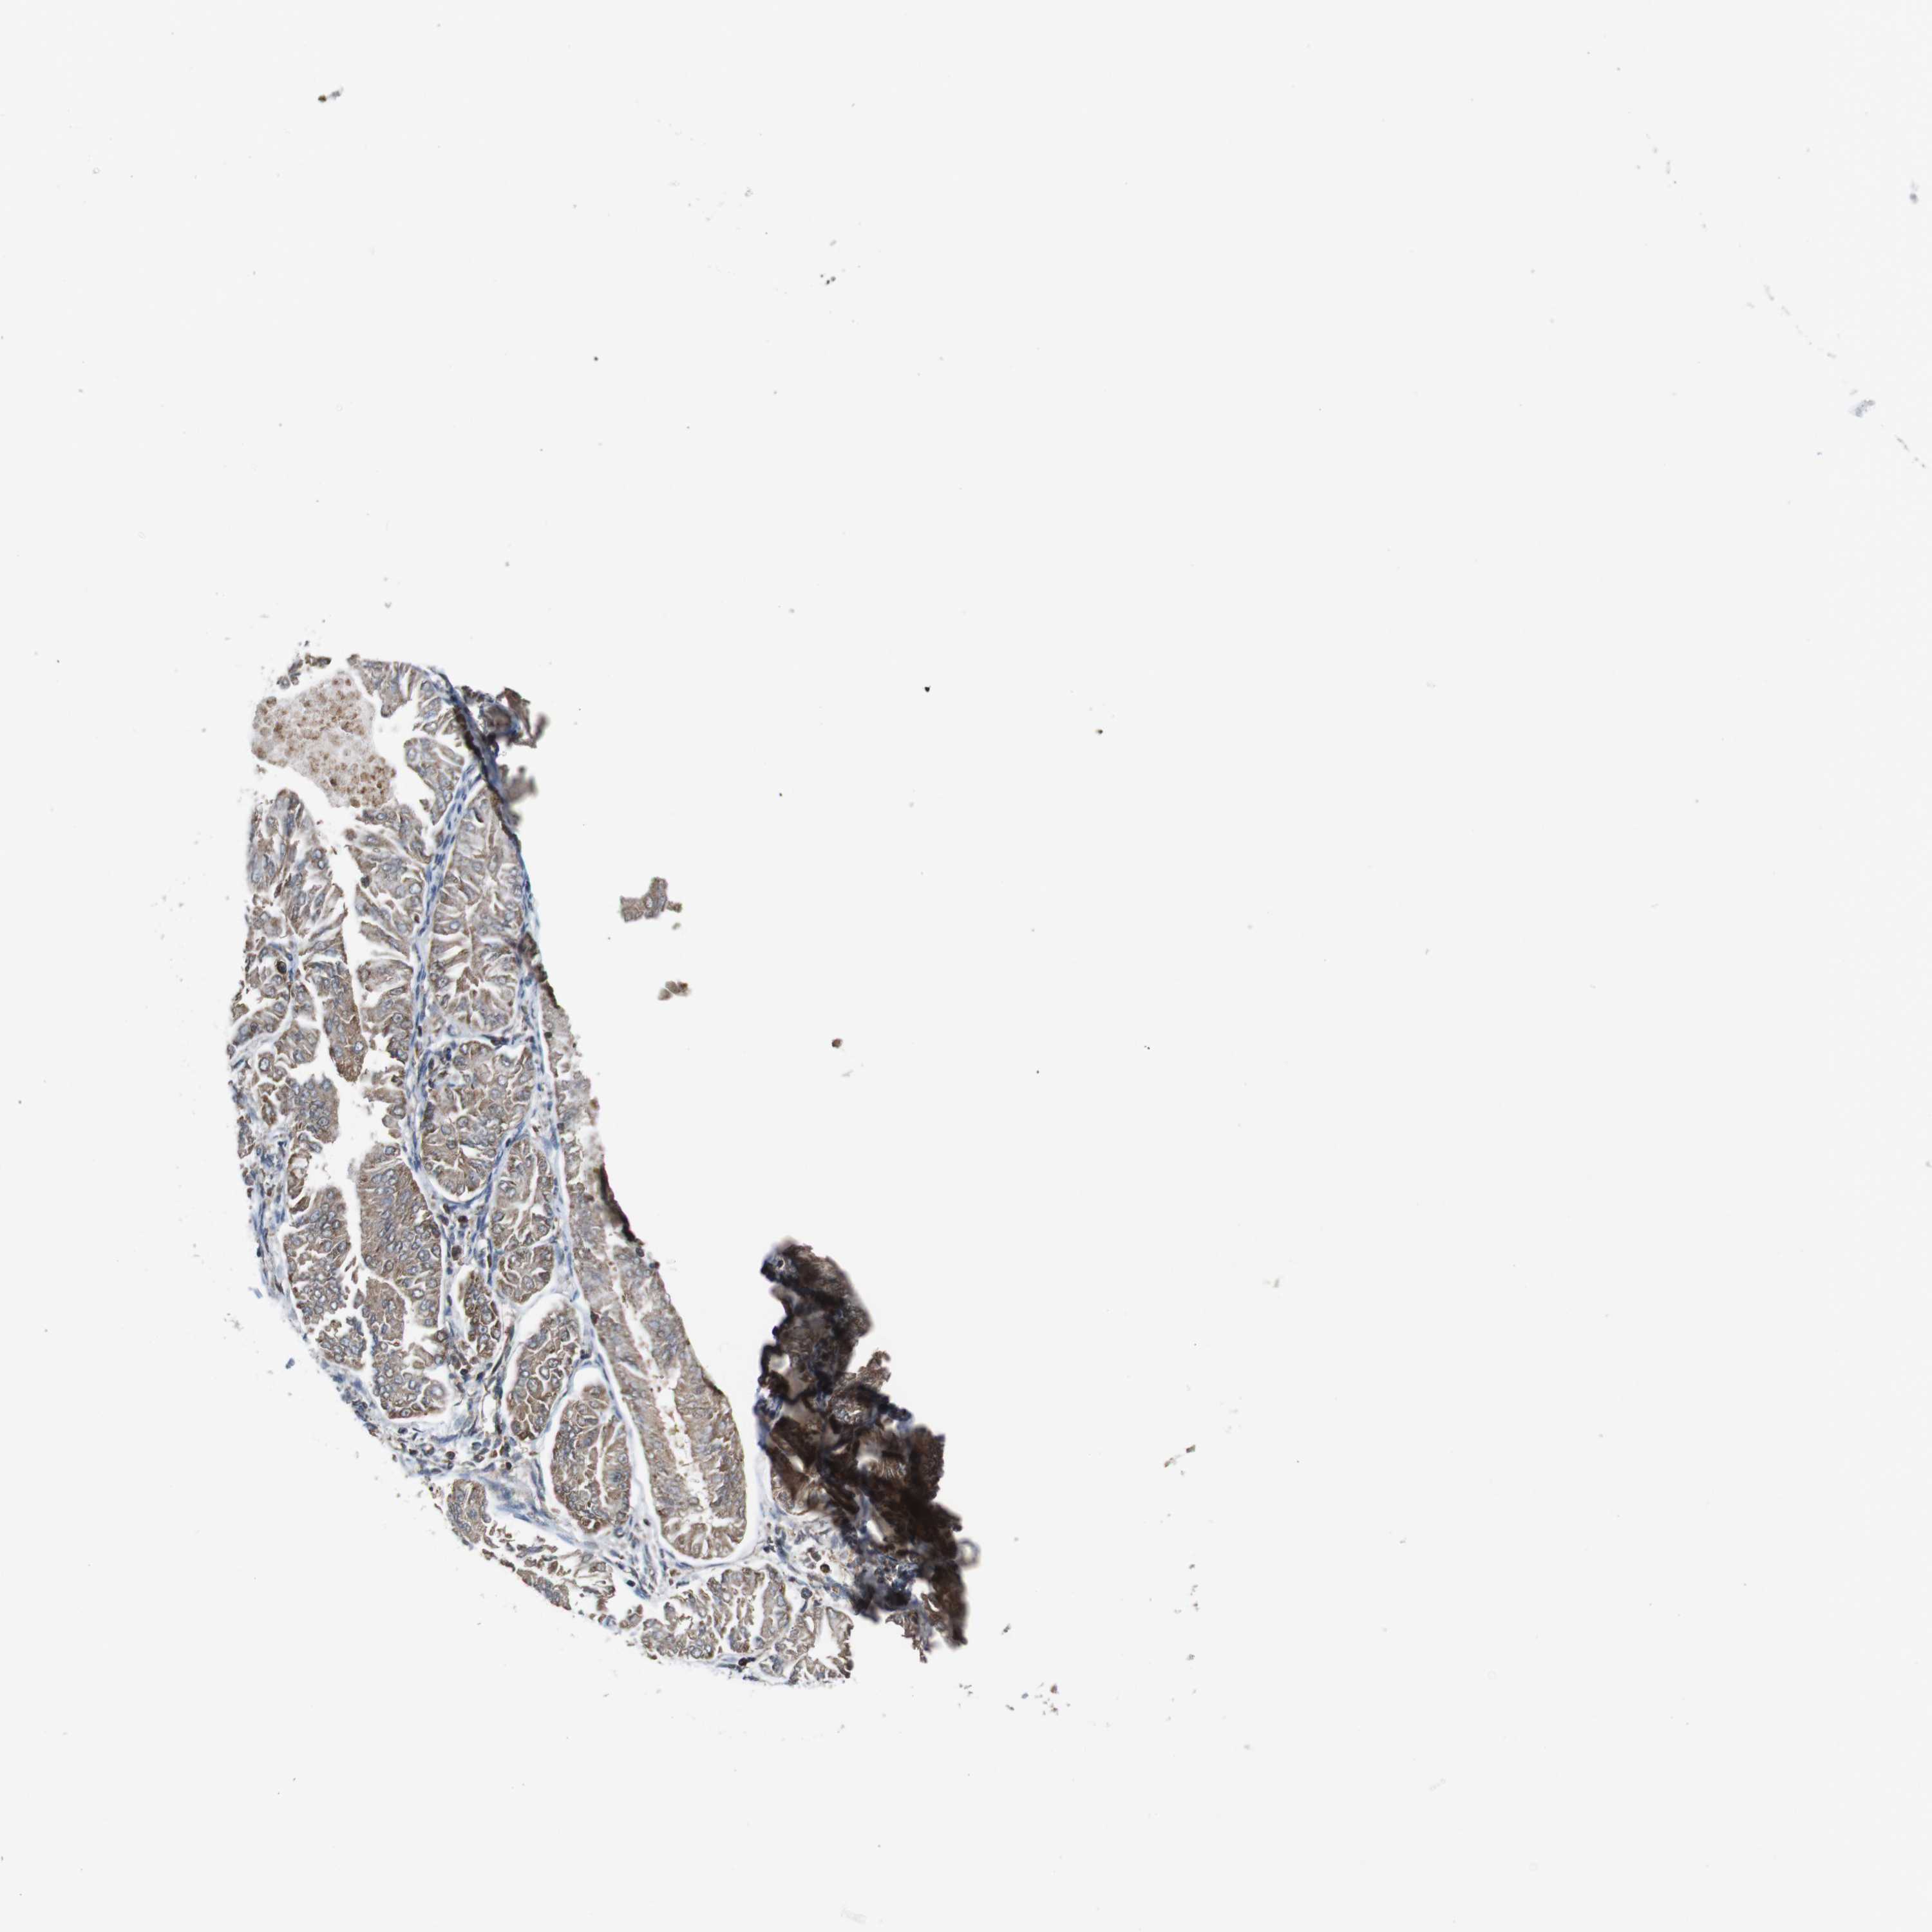

ENDOMETRIAL CANCER - Protein expressioni

A mouse-over function shows sample information and annotation data. Click on an image to view it in a full screen mode. Samples can be filtered based on level of antibody staining by selecting one or several of the following categories: high, medium, low and not detected. The assay and annotation is described here.

Note that samples used for immunohistochemistry by the Human Protein Atlas do not correspond to samples in the TCGA dataset.

Antibody stainingi

Antibody staining in the annotated cell types in the current human tissue is reported as not detected, low, medium, or high, based on conventional immunohistochemistry profiling in selected tissues. This score is based on the combination of the staining intensity and fraction of stained cells.

Each image is clickable and will lead to virtual microscopy that enables deeper exploration of all samples and also displays staining intensity scores, fraction scores and subcellular localization as well as patient and tissue information for each sample.

Antibody HPA007043

Antibody HPA007044

Antibody CAB010052

Staining

High

Medium

Low

Not detected

Intensity

Strong

Moderate

Weak

Negative

Quantity

>75%

75%-25%

<25%

None

Location

Nuclear

Cytoplasmic/membranous

Cytoplasmic/membranous,nuclear

Adenocarcinoma, NOS